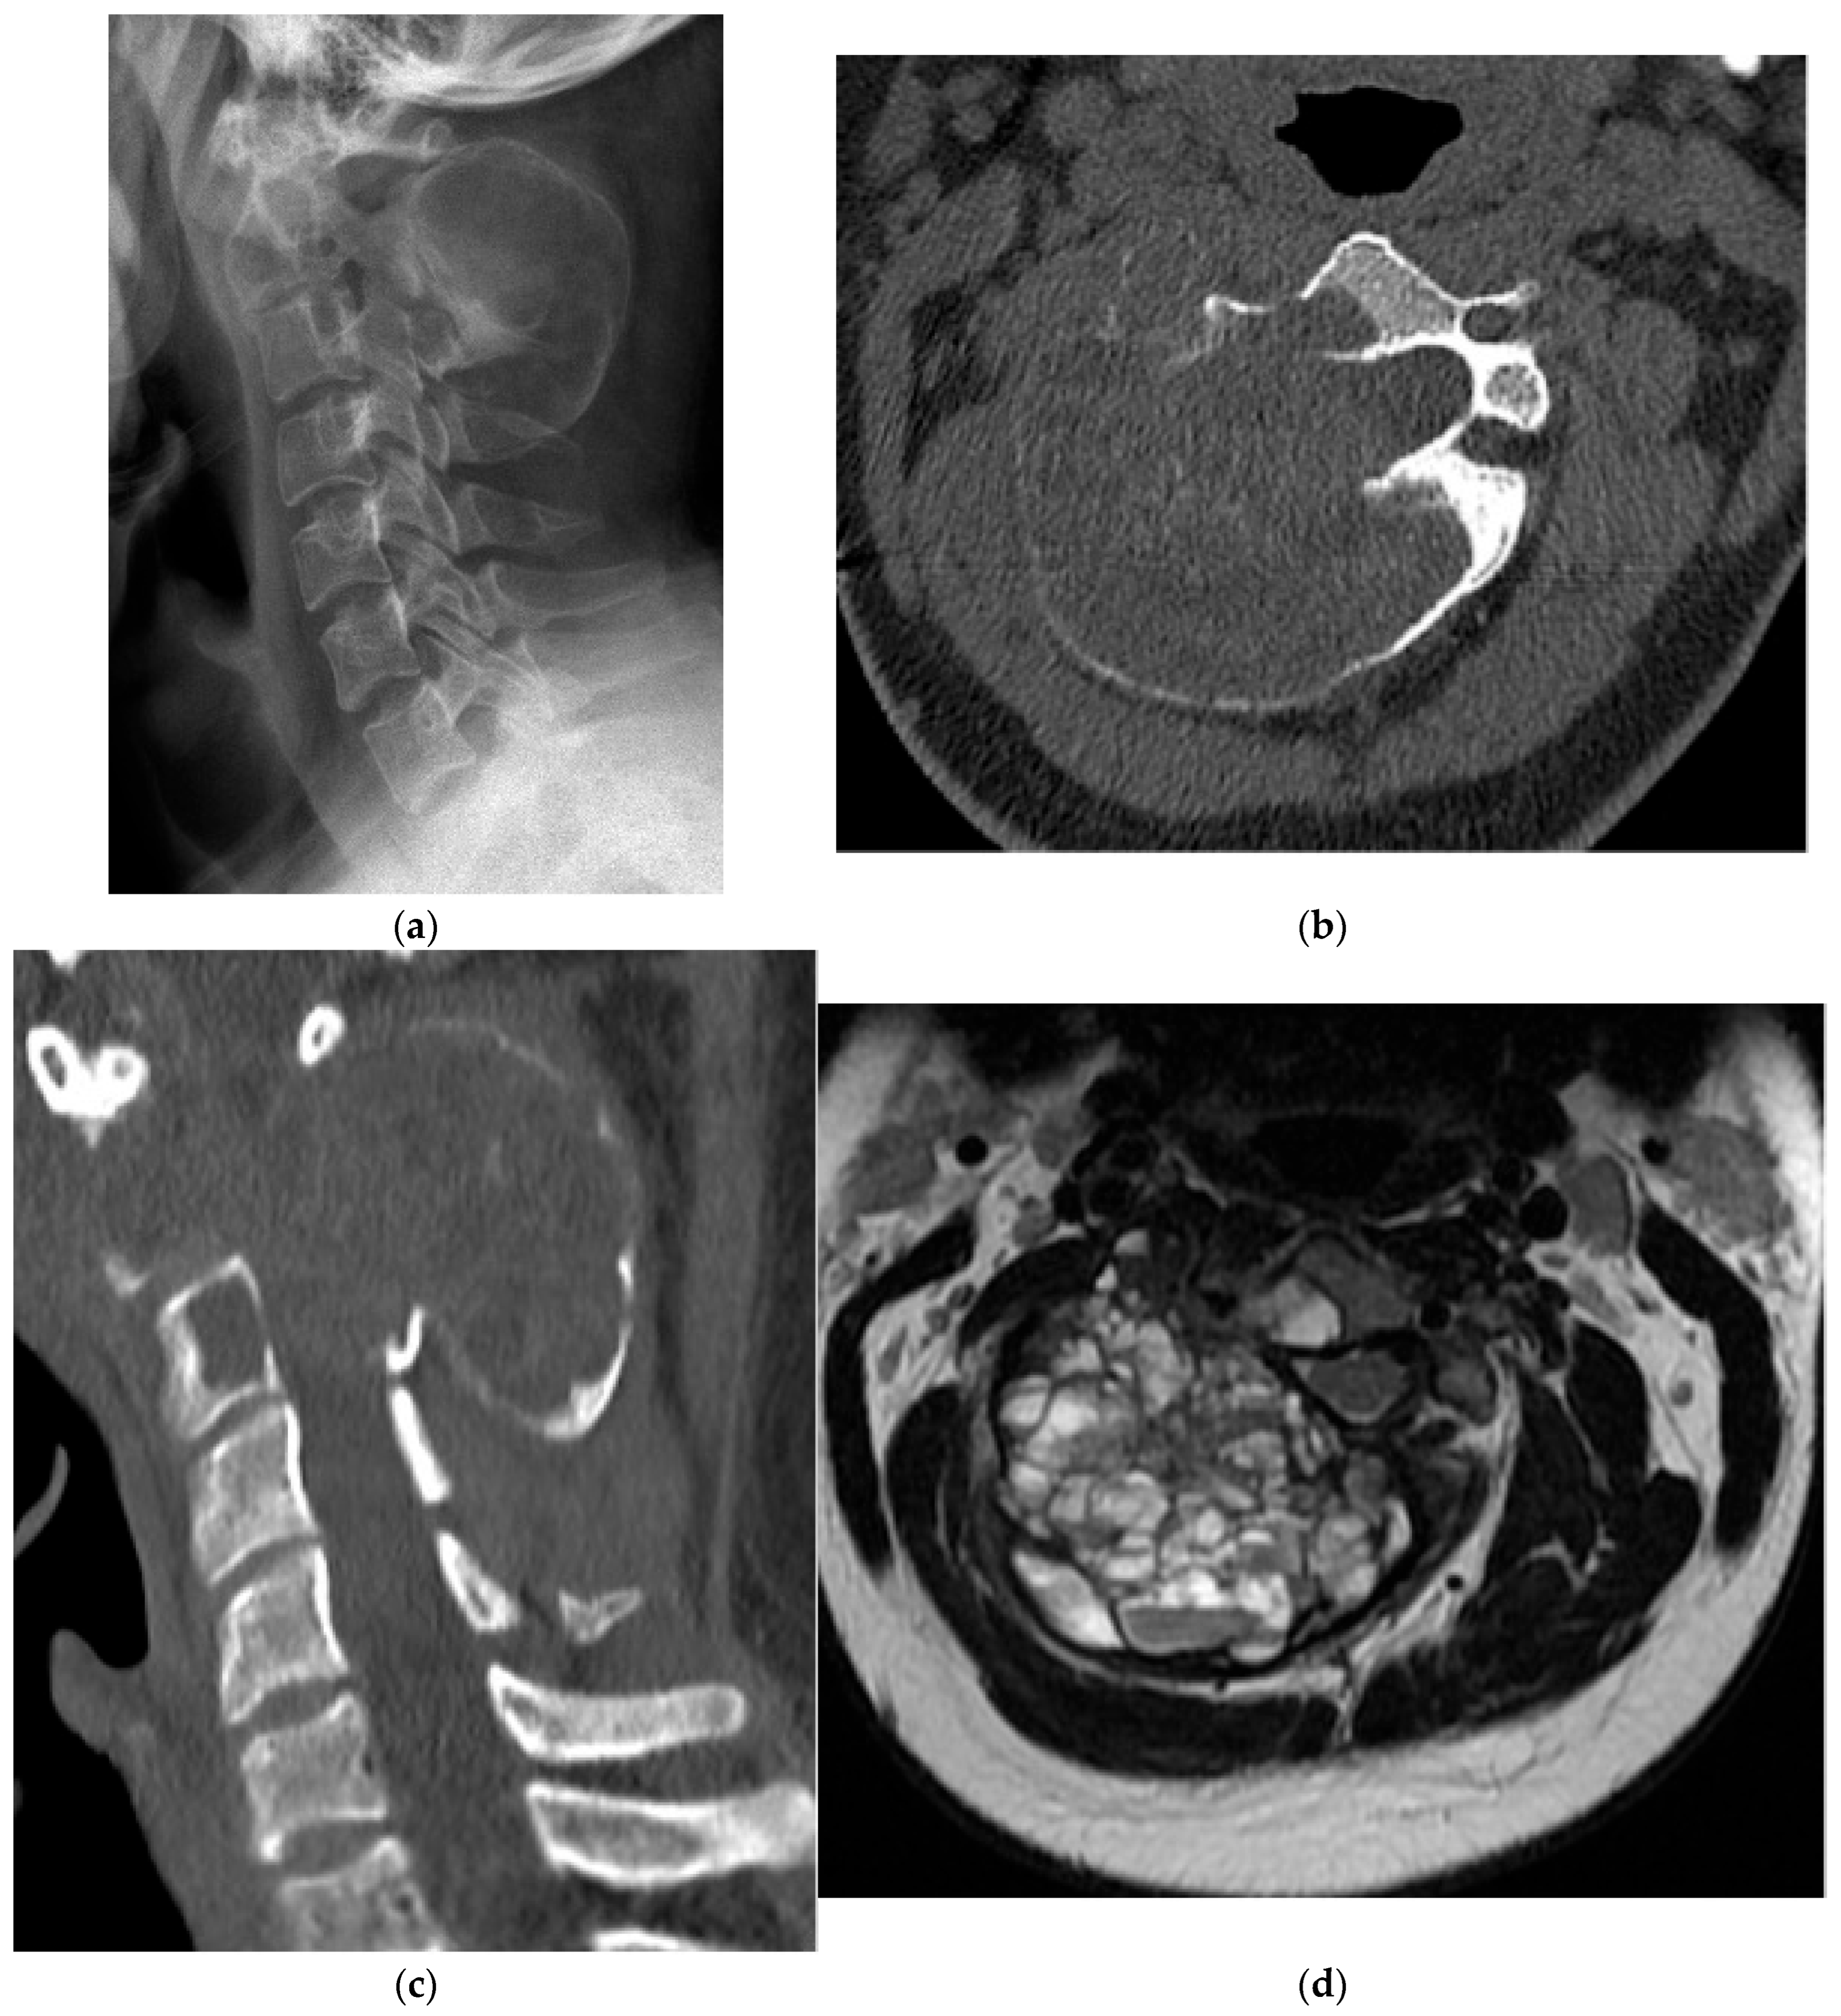

2.2.1. Osteochondroma